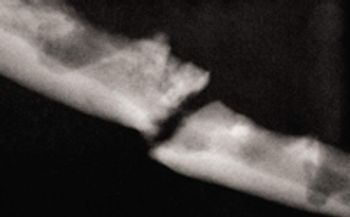

Chronicling the progression of periodontal bone destruction resulting in mandibular fractures in a dog.